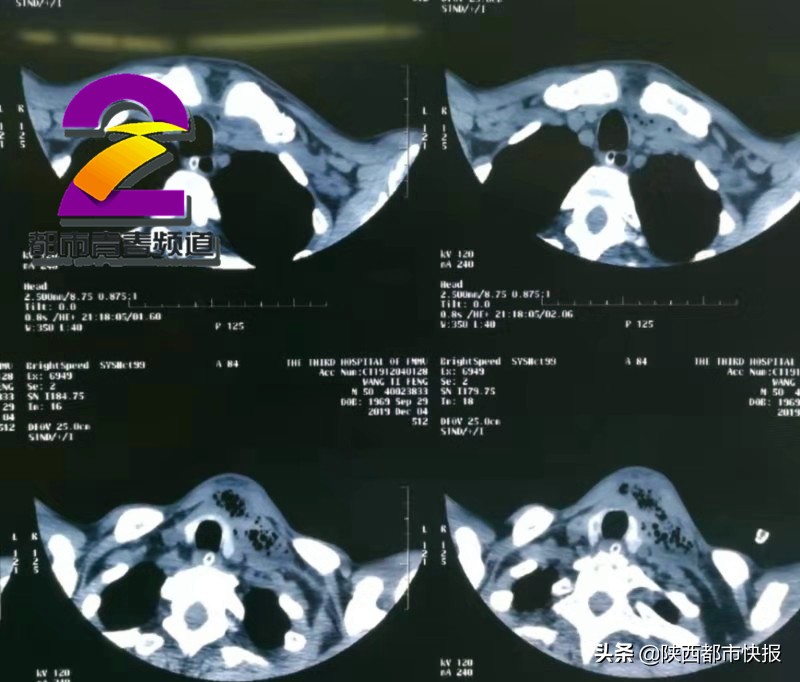

12月4号,西安大兴医院急诊科收治一名男性病人。病人因患牙病疼痛难忍,意识已经昏迷,并伴有高烧、呼吸困难等症状。西安大兴医院耳鼻咽喉颌面外科主任马戈介绍,当时患者情况已经非常紧急,牙疼已经导致颌面部、颈部腔隙感染,形成了大面积的脓包。马戈介绍,通过患者的头颈部CT能够清楚看到,脓肿已经从颌下、颏下、颈前一直到锁骨深面,再不切开引流,脓肿很快就要侵入纵膈。如果手术不及时,脓液将会进入胸腔,继而引发全身感染,出现电解质紊乱、败血症等并发症。严重的话,甚至会危及生命。